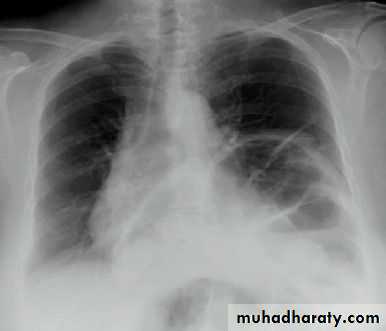

Pneumothorax

Severe dyspnea with shock